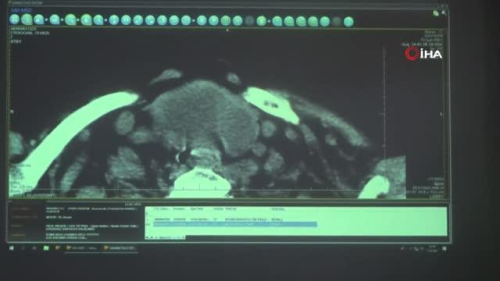

Kitlenin soluk borusuna baskı yapması müdahaleyi zorlaştırdı Anesteziyoloji ve Reanimasyon Anabilim Dalı Öğretim Üyesi Dr. Dilek Okyay, ameliyat süresince hastanın nefes alabilme güvenliğini sağlamanın önemine dikkat çekti. Okyay, "Bizim için önemli olan kısımlar şunlardı. Öncelikle hastadan bahsedelim. 77 yaşında kadın hastamız. Nefes darlığı şikayetiyle hastanemize başvuruyor. Üç dört gündür şikayetleri artmış. Neticede kronik obstrüktif akciğer hastalığı var. Bu da bizim için sıkıntı oluşturan bir durumdu. Ameliyata geldiğinde muayene ettiğimizde hastanın soluk borusuna basan bir kitlesi olduğunu gördük. Tomografi tetkiklerinde. Bu bizim için hakikaten önemli bir noktaydı. Çünkü anestezinin görevi ameliyat sırasınca hastanın havayolunun güvenliğini de sağlayabilmek. Bize bunu sağlayabilecek alan çok azdı. Bunu bilerek gerekli konsültasyonları isteyerek hastamızı en optimum koşulda ameliyata hazırlamaya amaçladık. Küçük bir alanda hastayı havalandırabilmeyi, havayolunu güvenlik altına almayı sağladık. Cerrahi ekibe hastamızı başarılı şekilde teslim ettik. Ameliyat süresince de herhangi bir sıkıntı olmadan ameliyatımızı sürdürdük" şeklinde konuştu.

Ereğli ilçesinde yalnız başına yaşayan 77 yaşındaki Zehra Erdoğan'ın 8 yıl önce multinodüler guatr rahatsızlığına yaşamaya başladı. Soluk borusuna baskı yapan nodül sebebiyle nefes almakta, konuşmakta zorluk yaşayan yaşlı kadın, ameliyatın riski görülmesi sebebiyle başvurduğu hastanelerde cerrahi müdahale yapılamadı. Oksijen tüpü ile yaşamaya çalışan kadın yaklaşık bir hafta önce yeniden rahatsızlandı. Oksijen değerlerinin düşmesi ve karbondioksit birikimi sebebiyle acil müdahale altına alınan Erdoğan için zorlu bir ameliyat süreci başladı. Zonguldak Bülent Ecevit Üniversitesi Uygulama ve Araştırma Hastanesi'nde tedavi altına alınan Erdoğan, 4.5 santimetreye 7 santimetre büyüklüğündeki kitlenin 3.5 saatlik zorlu bir ameliyatla alınmasıyla yeniden sağlığına kavuştu. Yıllar sonra yeniden rahatlıkla nefes alan kadın, sevincini kendisini ameliyat eden doktorlar ile paylaştı. 77 yaşındaki hastanın ameliyatını ise ZBEÜ Tıp Fakültesi Cerrahi Tıp Bölümleri Kulak Burun Boğaz Anabilim Dalı Öğretim Üyeleri Dr. Ergin Bilgin, Dr. Deniz Baklacı, Anesteziyoloji ve Reanimasyon Anabilim Dalı Öğretim Üyesi Dr. Dilek Okyay, hemşire ve diğer sağlık personelinden oluşan ekip gerçekleştirdi.